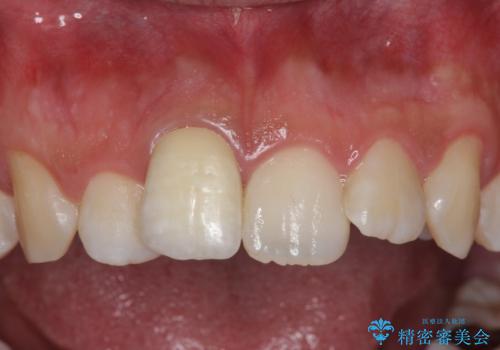

その際、支障がでないように、患者様と相談し、他の歯を削って並びを整えるようなことはせず、前歯の角度はそれなりにそろえる形にしました。

神経が死んでしまった歯は時間がたつと変色してきてしまいます、セラミックでかぶせると色を改善することが可能です。